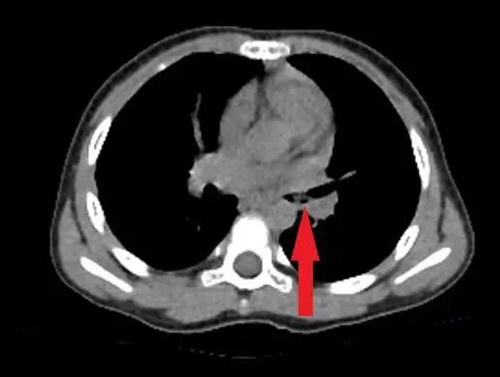

接診醫(yī)生詢問孩子病史,為其完善胸部CT、重建氣道,明確異物位置,發(fā)現(xiàn)小雨的左側(cè)支氣管內(nèi)有異物。